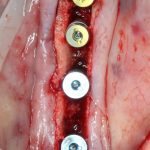

Установка имплантатов.

Напомню, что для этой работы я выбрал субкрестальные имплантаты Ankylos C/X. Они прекрасно сочетаются с любым методом остеопластики.

Я не планирую установку супраструктур или коронок, поэтому на уровень первичной стабильности можно положить болт. Даже наоборот — чем меньше крутящий момент при установке, тем лучше. Для имплантатов Ankylos и подобных им, это особенно важно. В общем, момент силы при установке — не более 10-15 Нсм.

Ремарка: имплантаты с предустановленными имплантодержателями хороши тем, что с ними легко контролировать позиционирование имплантатов. В случае с Ankylos С/Х - еще и крутящий момент. Имплантодержатель должен отсоединяться от имплантата с легким щелчком. Если его клинит, и тебе приходится прикладывать для этого усилия, то ты, однозначно, превысил момент силы во время установки имплантата. Следовательно, жди проблем.

Глянем на то, что получилось: